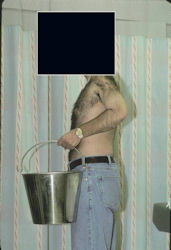

Examples of radical limb sparing surgeries for osteosarcomas in various anatomic locations (distal femur, proximal tibia, proximal humerus, scapula)

In each case, the tumor and bone from which it arose were resected. This required meticulous dissection, mobilization and preservation of adjacent pertinent neurovascular structures. In each case presented here, the defect was reconstructed with a special modular segmental tumor prosthesis. This also replaces the adjacent joint in many instances.

Proximal Humerus: Radical Limb Sparing Extra-Articular Resection and Prosethetic Reconstruction